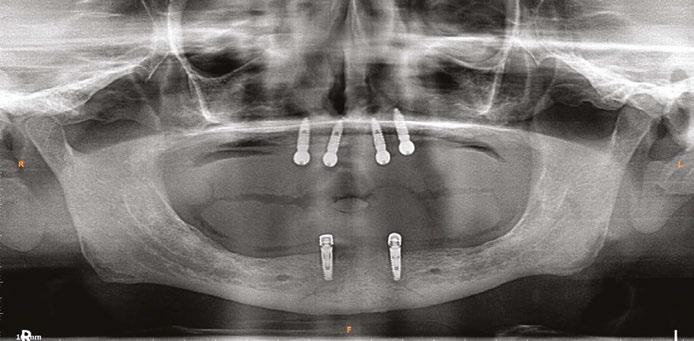

A 59-year-old male reported to the dental office with missing maxillary teeth due to poor oral hygiene. Treatment planning was done for All-on-4 implant placements followed by prosthesis. A complete medical history was obtained and was negative for any significant medical problems. The patient denied being allergic to any medication as well. The patient agreed to the implant placement and was advised to have an orthopantomogram (Figure 1).

on the crest of the ridge in the region of teeth Nos. 15-25. While creating the incision, bleeding was noticed in the region of tooth No. 15 which intensified during the flap reflection (Figure 2). Bleeding was pulsatile, indicating an arterial bleed. Initially attempts to control bleeding included a pressure pack and ice pack, and the bleeder was isolated and the vessel ligated (Figure 3). The bleeding could be controlled, and the procedure was completed by placing four Bioner implants (Bioner, Spain), size 4/10 mm. Sutures were placed, and patient was kept on basic medication for pain and infection control. Immediately after the surgery, the patient was advised to get a CBCT. As shown in Figure 4, a coronal view and Figure 4B (yellow arrows), the position of the artery can be seen.

In the follow-up sessions, the patient was comfortable, but did complain of mild swelling which subsided within 4-5 days. A post-op CBCT showed excellent recovery, bone width, and proper implant placement (Figure 5).

Figure 1: Pre-op panoramic radiograph

Figure 2 (left): Alveolar antral artery (AAA). Figure 3 (center): The artery has been ligated with suture. Figures 4A and 4B (right): CBCT post-implant placement and position of the artery coronally (top). 4B. Showing the position of alveolar antral artery (AAA) in relation to implant placement as indicated by the yellow arrows (bottom)

Figure 5: Panoramic radiograph following implant placement